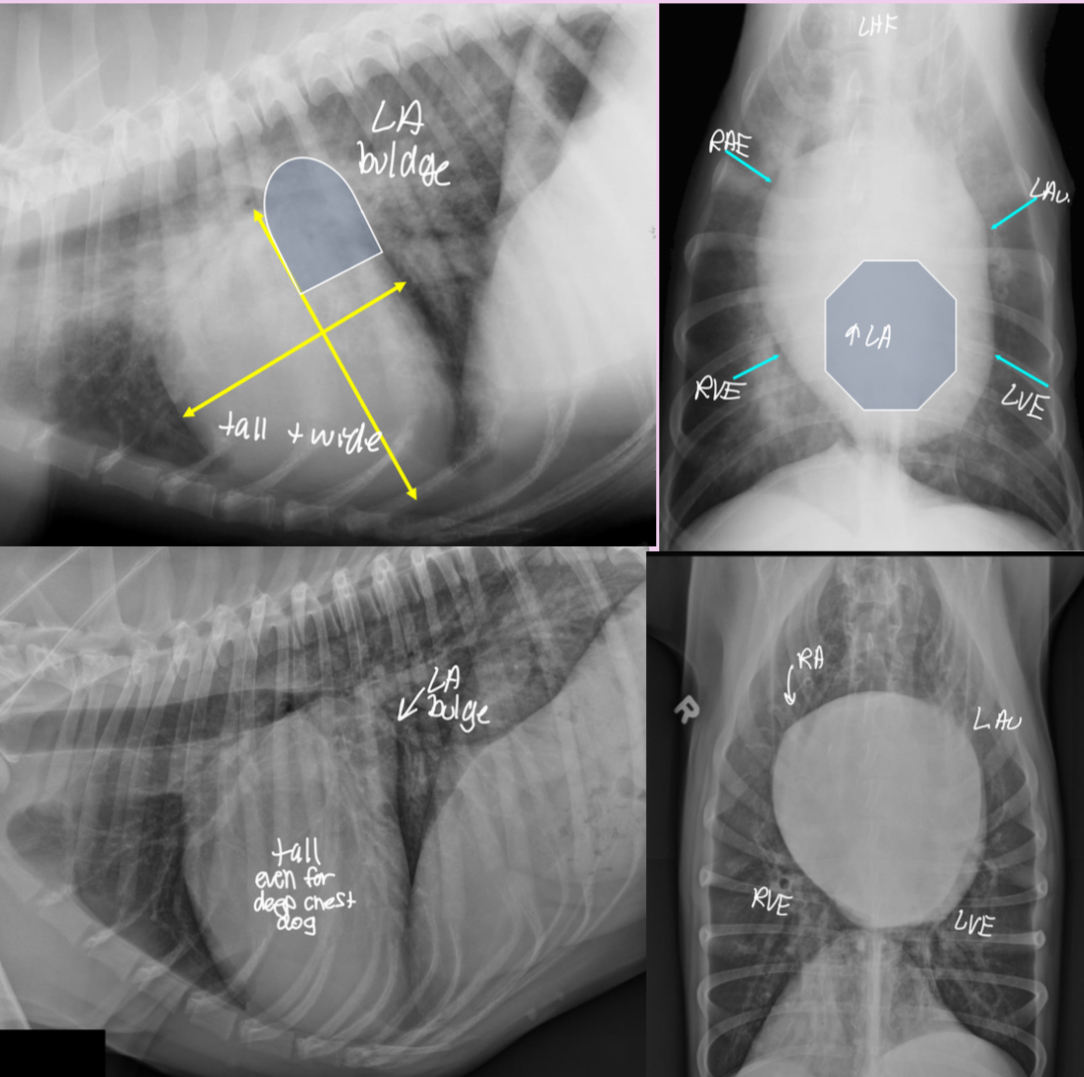

3 features of LAE on lateral

-dorsal displacement of main stem bronchi by a hunchback bump

-increased cd.dorsal cardiac border

-loss of cd.cardiac waist - straightening of cd.cardiac margin

3 features of LAE on DV

-double opacity sign

-separation of main stem bronchi

-LA bulge at 2:30-3 o’clock

3 features LVE on lateral

-tall heart (>2/3 DV diameter)

-dorsal displacement of trachea (almost parallel to spine)

-straightening of cd. border of heart

3 features of LVE VD

-elongation of cardiac silhouette

-deviation of apex to the left

-bulge at 3-5 o’clock

Features of generalized cardiomegaly in dogs and what disease is associated with this?

-combo roentgen signs involving L and R cardiac chambers

-dogs often get mitral dz which results in both L+R heart enlargement

-tall + wide, sternal contact

what part of the heart is enlarged in this dog

Generalized (whole thing)